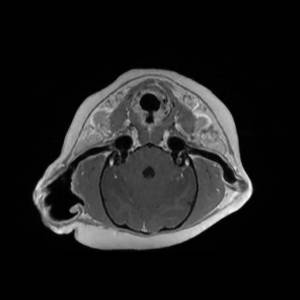

Main Gallery

Playing with a photo gallery function. It is possible to have multiple galleries, each within a namespace.